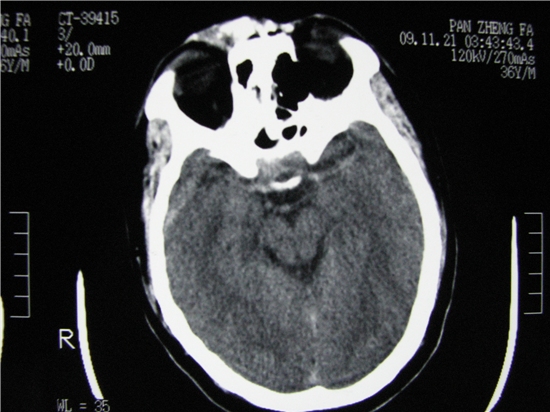

标题: CT23231:男 32岁 车祸伤,鼻腔内出血明显。 [打印本页]

标题: CT23231:男 32岁 车祸伤,鼻腔内出血明显。

额窦里是什么,骨窗怎么不清晰,是不窗宽窗位的事。

软组织及额窦内异物

额窦内及额部软组织内可见多发游离类骨质密度影,考虑额骨骨折可能。

鼻骨层面较少,无法判断鼻骨。

额窦致密骨瘤,前额部及右顶部头皮损伤伴异物存留

左侧额骨、鼻骨骨折,头面部软组织肿胀。

左侧额骨、鼻骨骨折,额窦内的应该是游离骨块

额窦致密骨瘤,